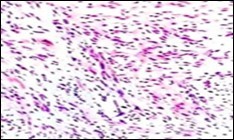

Figure 6.Soft tissue perineurioma with foci of spindle cells with wavy nuclei and an admixture of myxoid and collagenous stroma 15.

Figure 7.Soft tissue perineurioma with an abundance of collagen fibrils intermixed with a neural element with bipolar cells with elongated cytoplasm and wavy nuclei 16.

Figure 8.Soft tissue perineurioma with neural cells exemplifying elongated cytoplasmic processes, slender, wavy nuclei and an abundance of collagenous stroma 17.

Soft tissue perineurioma can be indicated if a myxoid lesion exhibits a distinctive storiform or fascicular pattern of tumour evolution. Cellular proliferation can be composed of spindle cells, characteristically demonstrating elongated, thin, delicate, bipolar cytoplasmic processes, a pale-staining, eosinophilic cytoplasm with wavy or tapering nuclei and a finely dispersed nuclear chromatin.

The neoplasm can depict perivascular whorls. Mitotic activity can be observed enumerated as 0-13 /30 high power fields, although around 65% tumours are devoid of mitotic activity. Neoplasms of extensive duration can exhibit foci of degenerative atypia with modifications such as nuclear pleomorphism and nuclear hyperchromasia with intracytoplasmic and intra-nuclear inclusions. Tumour necrosis is generally absent5, 6. Microscopically, a perineurioma composed of bland, ovoid to spindle-shaped cells with elongated, slender nuclei and elongated, bipolar cytoplasmic processes can delineate a storiform, lamellar or a whorled pattern or perivascular aggregates of neoplastic cells are configured, disseminated in a collagenous or focally myxoid stroma. Lesions such as a hybrid schwannoma or perineurioma with features intermediate betwixt a schwannoma and perineurioma can be discerned. Characteristically, bland, ovoid to thinly elliptical, spindle-shaped cells with elongated, delicate, bipolar, cytoplasmic processes are exemplified with a storiform or whorled architectural pattern. Intervening stroma can be myxoid, collagenous or myxo-collagenous5, 6.